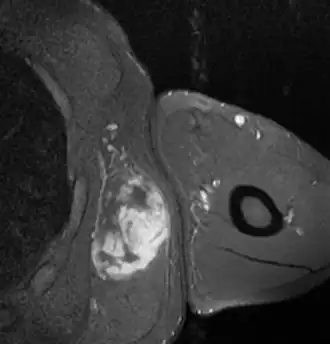

Liposarcoma

El liposarcoma es un tumor maligno de origen mesodérmico derivado del tejido adiposo. Es el sarcoma de partes blandas más frecuente.[1][2][3][4]

- Bien diferenciado: Liposarcoma bien diferenciado (WDLS) es el tipo más común de liposarcoma. Se define como un tumor de malignidad intermedia compuesto, totalmente o en parte, por adipocitos maduros que presentan variaciones significativas en su tamaño y, al menos, atipia nuclear focal, tanto en células estromales como lipoblastos. Representan el 40-50% de todos los LPS. Se presentan habitualmente en adultos de edad media-avanzada (máxima incidencia en la 6.ª década) y sin diferencias sexuales (1). Por orden de frecuencia, las localizaciones preferenciales son: extremidades (70%)–especialmente el muslo–, retroperitoneo (RP) (20%),área paratesticular y mediastino (10%).